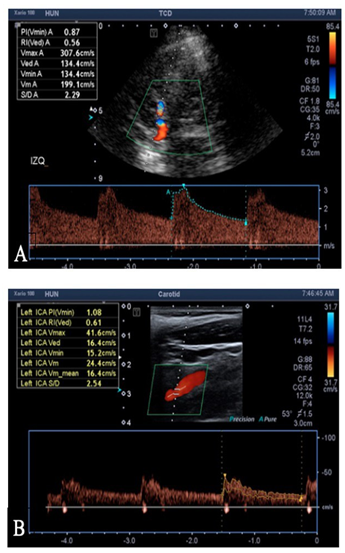

El índice de Lindegaard es la razón entre la velocidad media del flujo sanguíneo de la arteria cerebral media y la carótida interna. Se realiza mediante Doppler transcraneal y gradúa el vasoespasmo cerebral. Un índice menor a tres se considera como normal, entre tres a seis como vasoespasmo leve a moderado y mayor de seis, severo 3.

El día nueve el paciente presentó cefalea intensa y aumento del índice de Lindegaard izquierdo hasta 8,15 (figuras 2A-B). Por lo anterior, se realizó angiografía que mostró vasoespasmo en las arterias cerebrales anteriores y arteria cerebral media izquierda, por lo que se administró terapia de infusión intrarterial de nimodipino con mejoría clínica y angiográfica. En el cuadro 1 se aprecia la correlación entre el déficit neurológico, el índice de Lindegaard elevado (mayor a seis) y la presencia del vasoespasmo documentado angiográficamente.